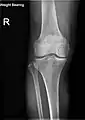

Knee X-ray

Knee X-ray (weight bearing)

Knee X-ray (weight bearing, flexion)